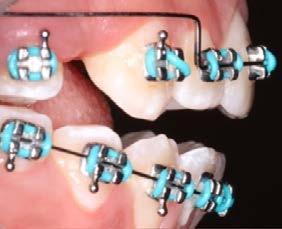

Caso clínico: paciente femenino de 19 años, patrón dolicofacial, perfil convexo, clase II esqueletal debido a una retrusión mandibular, mordida abierta anterior esqueletal, clase II molar, clase canina no establecida por mordida abierta, apiñamiento severo superior e inferior y deglución atípica.

Resultados: obtención de una clase canina I y clase molar II funcional, se corrigieron las sobremordidas horizontal y vertical, y se logró la coincidencia de líneas medias facial y dental. El manejo de la mordida abierta anterior se llevó a cabo por medio de la corrección del hábito de deglución atípica con la ayuda de spikes de resina, elásticos intermaxilares y arcos utility, y se obtuvieron buenos resultados estéticos, dentales y funcionales.